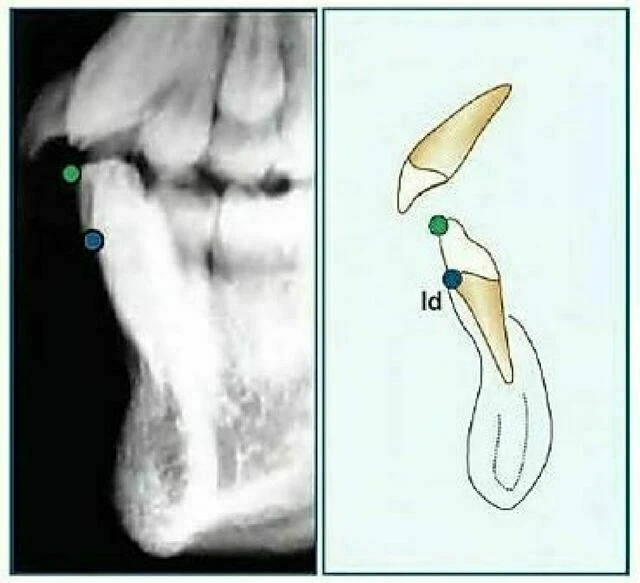

Insision Inferius (Ii): Đỉnh rìa cắn của răng cửa giữa hàm dưới nằm về phía ngoài nhất.

Infradentale (Id): Điểm nằm ở vị trí trên trước nhất của xương ổ răng hàm dưới, thường tìm thấy gần đường nối xi măng – men răng của răng cửa giữa hàm dưới. Còn được gọi là điểm Inferior Prosthion.

Supramentale (điểm “B”): Là điểm nằm ở vị trí sau nhất ở đường cong xương hàm dưới nối từ Infradentale đến Pogonion. Điểm “B” thường tìm thấy gần 1/3 chóp các chân răng cửa hàm dưới và có thể bị che khuất trong suốt quá trình các răng này mọc. Khi nét mặt nhìn nghiêng vùng cằm không lõm thì không thể xác định được điểm “B”.